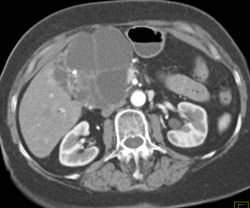

Diagnosis

Cystadenoma